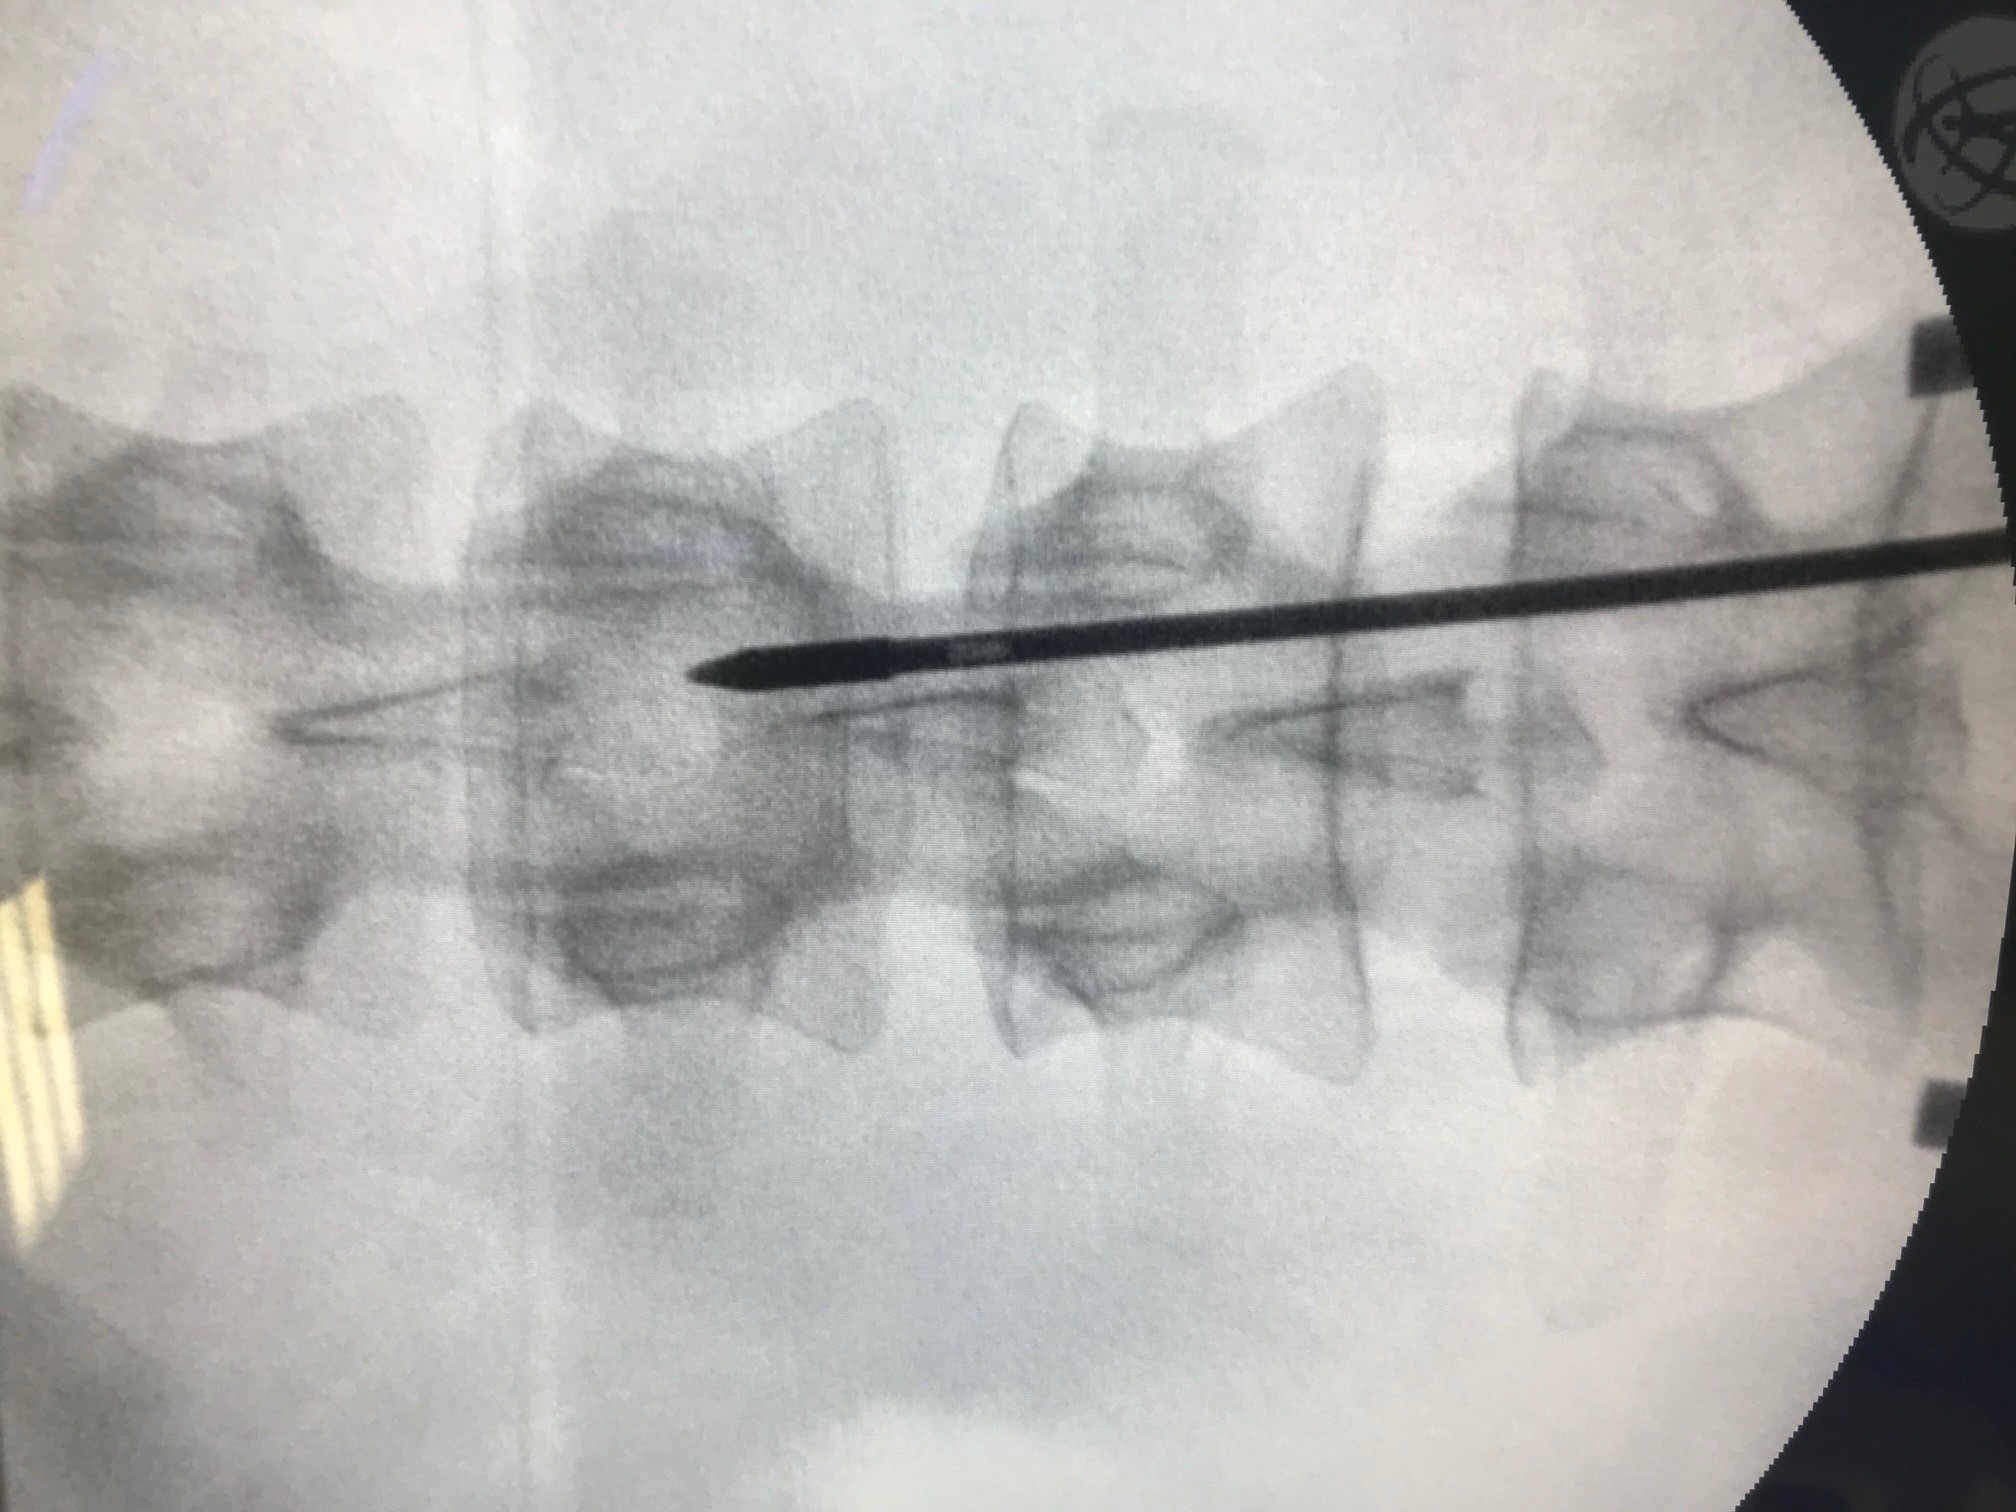

as Verfahren wird Neuromodulation genannt (SCS – Spinal Cord Stimulation). Über eine minimalinvasive Operation wird eine Elektrode auf das Rückenmark aufgelegt und hierüber die Bahnen, welche für die Schmerzweiterleitung zuständig sind, beeinflusst.

Die Bilder zeigen einen 31 jährigen Patienten, der in der Vorgeschichte bereits 2 Mal aufgrund eines Bandscheibenvorfalls operiert wurde.

Bereits vor beiden Operationen bestanden ein Taubheitsgefühl und eine Schwäche für die Fußmuskulatur. Nach dem zweiten Eingriff bestanden weiterhin Schmerzen im Bein.

In einem dann durchgeführten MRT zeigte sich jedoch, dass der Nerv völlig frei war und nicht mehr durch Bandscheibengewebe gedrückt wurde. Nach weiterer erfolgloser konservativer Therapie (Reha, Medikamente und Infiltrationen) bestand dann die Indikation für einen Schmerzeingriff.

Auf den Bildern sehen Sie die Anlage einer Elektrode im Spinalkanal. Die Elektrode wird, unter Röntgenkontrolle auf der Haut die das Rückenmark umgibt, eingebracht und so weit nach oben geschoben, dass sie auf dem Areal zu Liegen kommt in dem die Schmerzen der Beine im Rückenmark verschaltet werden. Über ein hier aufgebautes elektromagnetisches Feld wird direkt auf die Schmerzweiterleitung eingewirkt und die Schmerzen im Bein werden „blockiert“.